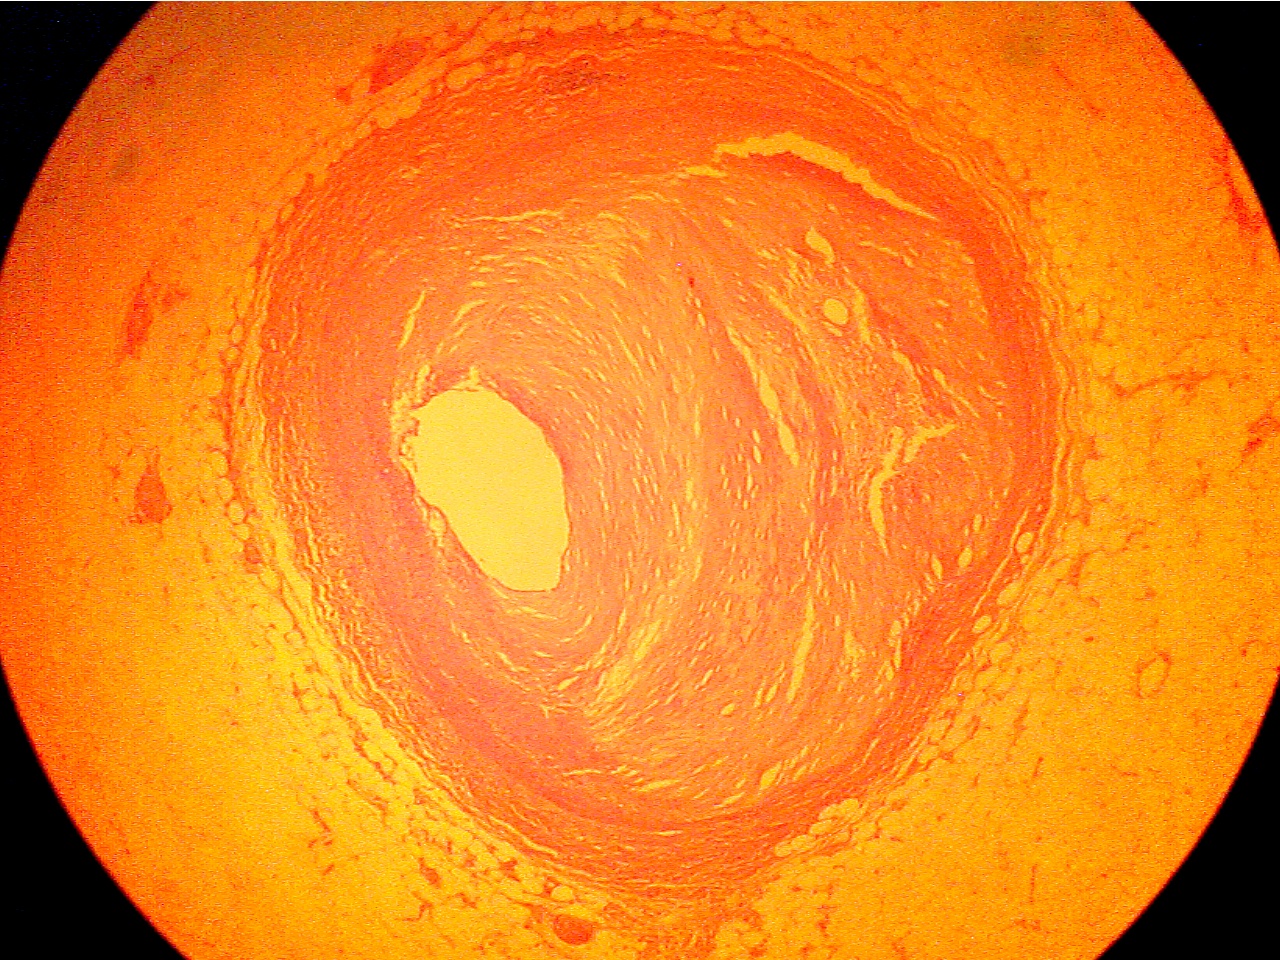

Atherosclerosis of Coronary Artery (PH 804, 813, 814)

First observe a slide of an early atherosclerotic lesion (PH 813). The

pink, noncellular material in the intima of the coronary artery is the

atherosclerotic

plaque. This lesion has already reduced the lumen by about 20%. Now

observe one of the later atherosclerotic plaques (PH 804 or PH 814).

Note the degree of occlusion by the lesion. It may take years for

plaque to reach this size.

Occlusive lesion

(40X1.0 - c1)

Lumen at far left of center, crystalline lesion fills center